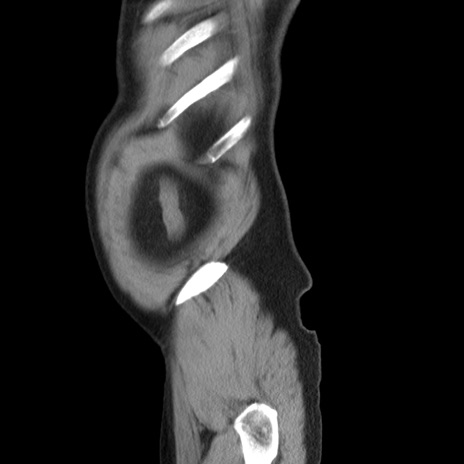

症例20(矢状断像)

【症例】 60歳代男性

【主訴】 腹部膨満、嘔吐

【現病歴】5日前頃より倦怠感を認め食事量減少し4日前の朝嘔吐、食事摂取困難となった。 3日前近医受診し点滴施行され整腸剤などを処方された。 当日他院を受診し、腹部膨満著明、炎症反応の上昇(CRP10.8、WBC11200)あり、紹介受診となる。

【身体所見】 意識JCS1 受け答えがはっきりしないBP 111/57mHg、 P 67bpm、、BT35.2°C、SpO2 97%(RA)、 腹部:膨隆、打診で鼓音あり、全体的に圧痛有り、腸蠕動音(-)、反跳痛ははっきりせず。

【データ】WBC 11400、CRP 14.20